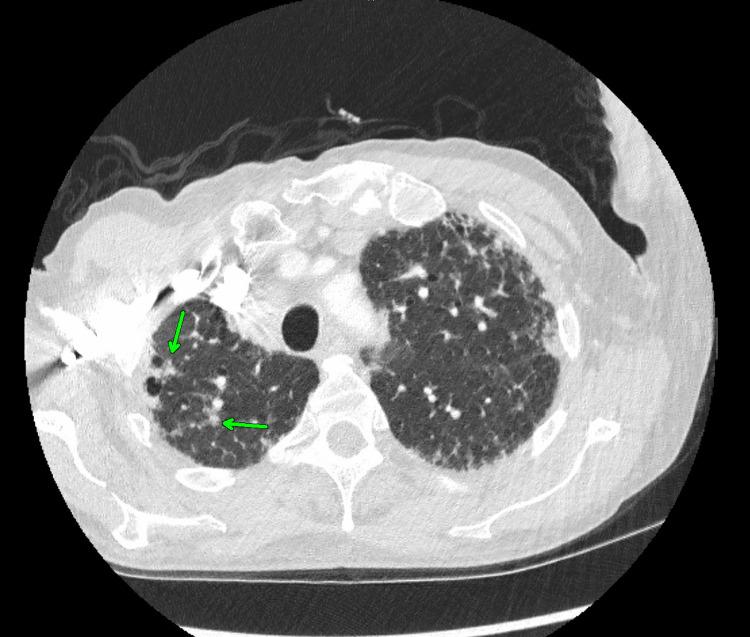

Histoplasmosis, a fungal infection caused by the inhalation of conidia spores, has been shown to cause disseminated disease in immunocompromised individuals. Disseminated histoplasmosis manifests as multi-system involvement including pulmonary and/or neurological disease. Imaging findings, such as pulmonary focal infiltrates, cavitary nodules, mediastinal, and hilar lymphadenopathy, are common. Here, we report a rare case of disseminated histoplasmosis in a 58-year-old immunocompetent male with no occupational exposure. This patient presented with primary adrenal insufficiency, and a subsequent CT-guided biopsy of the adrenal gland was performed and revealed numerous spores containing . This patient also suffered from numerous pulmonary and neurological derangements, which are likely sequelae of the disseminated fungal infection. Ultimately, the patient succumbed to their illness and died. Preventing such outcomes relies on early detection and prompt management, which are crucial in treating disseminated histoplasmosis. Increased awareness of atypical presentations can enhance patient outcomes and alleviate the impact of this severe fungal infection. This case not only underscores the importance of considering disseminated histoplasmosis in an immunocompetent patient presenting with unexplained weight loss and adrenal insufficiency but also contributes to the limited literature on disseminated histoplasmosis in immunocompetent individuals.

组织胞浆菌病是一种因吸入分生孢子而引起的真菌感染,已被证明会在免疫功能低下的个体中引发播散性疾病。播散性组织胞浆菌病表现为多系统受累,包括肺部和/或神经系统疾病。影像学表现,如肺部局灶性浸润、空洞性结节、纵隔和肺门淋巴结肿大,较为常见。在此,我们报告一例罕见的播散性组织胞浆菌病病例,患者为一名58岁免疫功能正常的男性,无职业暴露史。该患者出现原发性肾上腺功能不全,随后进行了CT引导下的肾上腺活检,结果显示有大量含孢子的组织。该患者还患有多种肺部和神经系统紊乱,这可能是播散性真菌感染的后遗症。最终,患者因病死亡。预防此类后果依赖于早期发现和及时治疗,这对治疗播散性组织胞浆菌病至关重要。提高对非典型表现的认识可以改善患者预后,减轻这种严重真菌感染的影响。该病例不仅强调了在出现不明原因体重减轻和肾上腺功能不全的免疫功能正常患者中考虑播散性组织胞浆菌病的重要性,也为免疫功能正常个体播散性组织胞浆菌病的有限文献增添了内容。